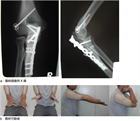

1. 直達外力による肘頭骨折と上腕三頭筋の牽引力によって起こる肘頭剝離骨折がある。

前者に対しては観血整復内固定術が行われることが多く、tension band wiring、intramedullary screw fixation、肘頭用アナトミカルロッキングプレートによるプレート骨接合術などの選択肢がある。

また後者に対する内固定法としては、骨片摘出+上腕三頭筋腱前進+その付着部の再縫着術が行われることが多い。